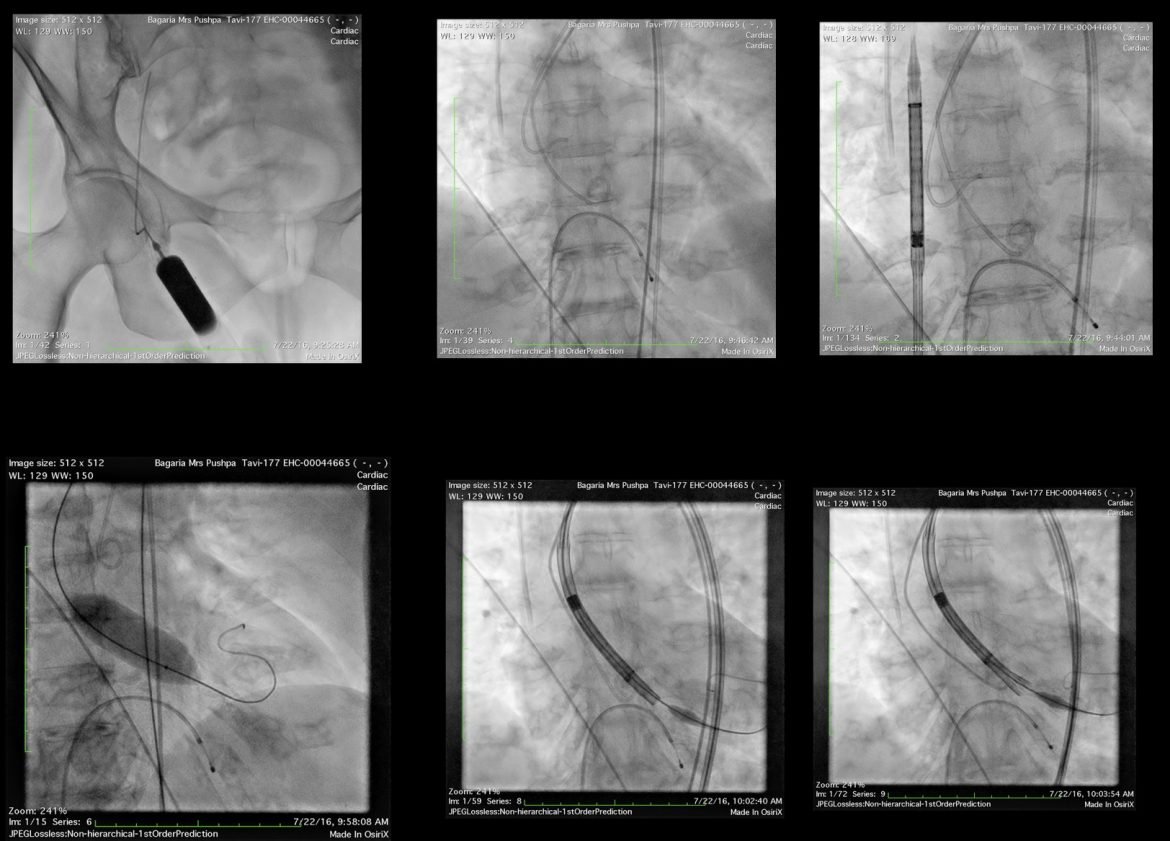

Dear All, It gives us immense pleasure to share that Dr. Ravinder Singh Rao was invited to AIIMS, New Delhi, to perform the first TAVI case of AIIMS. The procedure was done successfully without complications, and the patient was discharged on 3rd day. We would like to share this historical moment with you all. AIIMS is a premier institute in the country. Dr. Rao has the highest experience of TAVI with the safest outcome in the country.

It is the latest milestone in the field of interventional cardiology. This TAVR technique includes the alternate or implantation of an aortic valve with a new biological valve without even open heart surgery.